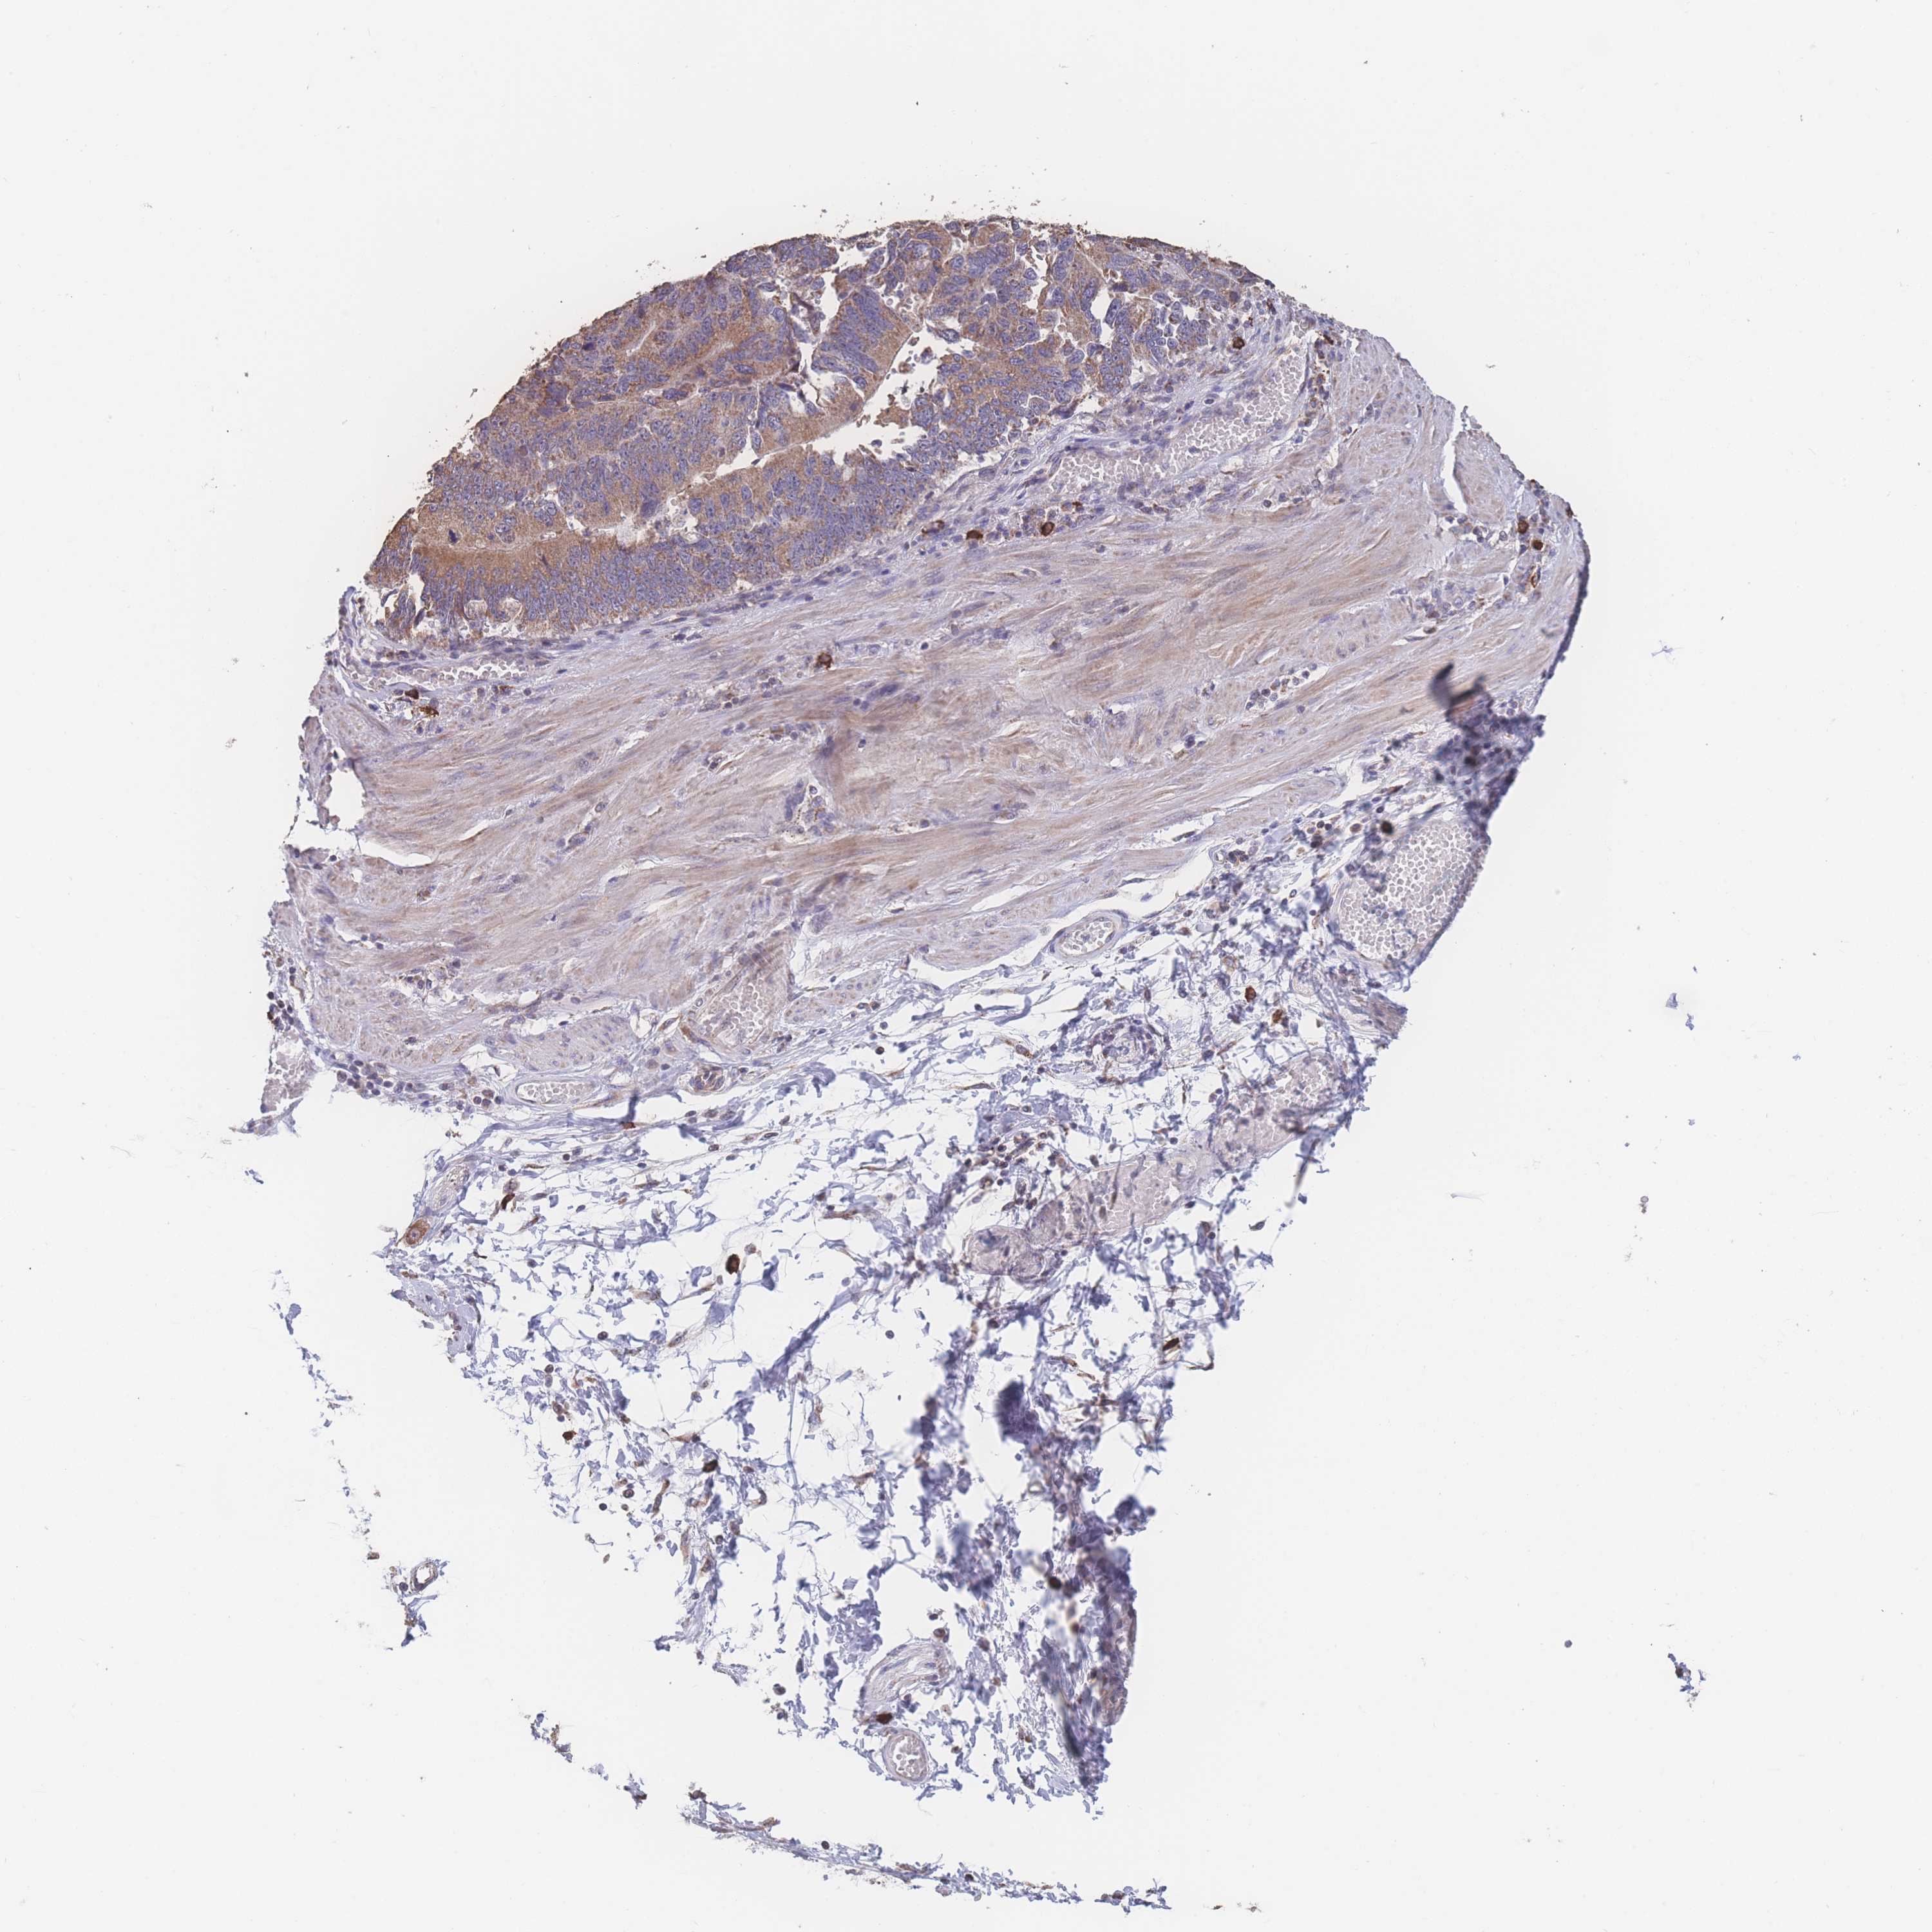

STOMACH CANCER - Protein expressioni

A mouse-over function shows sample information and annotation data. Click on an image to view it in a full screen mode. Samples can be filtered based on level of antibody staining by selecting one or several of the following categories: high, medium, low and not detected. The assay and annotation is described here.

Note that samples used for immunohistochemistry by the Human Protein Atlas do not correspond to samples in the TCGA dataset.

Antibody stainingi

Antibody staining in the annotated cell types in the current human tissue is reported as not detected, low, medium, or high, based on conventional immunohistochemistry profiling in selected tissues. This score is based on the combination of the staining intensity and fraction of stained cells.

Each image is clickable and will lead to virtual microscopy that enables deeper exploration of all samples and also displays staining intensity scores, fraction scores and subcellular localization as well as patient and tissue information for each sample.

Antibody HPA048980

Staining

High

Medium

Low

Not detected

Intensity

Strong

Moderate

Weak

Negative

Quantity

>75%

75%-25%

<25%

None

Location

Nuclear

Cytoplasmic/membranous

Cytoplasmic/membranous,nuclear

Adenocarcinoma, NOS